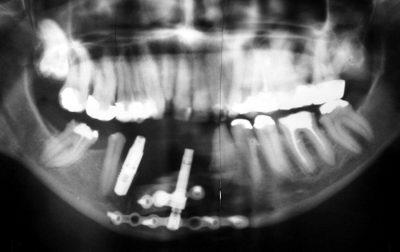

Obecně známá metoda v kostní chirurgii, která má za cíl provést změnu délky, šířky nebo výšky kosti se nazývá distrakce. Jednorázový nástroj, který se k distrakci používá je distraktor. Umožňuje chirurgicky kontrolovaně provádět tyto změny tvaru a velikosti kosti. Obvykle se distrakce provádí rozříznutím kosti ve směru kolmém na směr působení distrakce. Jedna část kosti se upevní nejčastěji prostřednictvím osteosyntetického materiálu (minidlahy různého tvaru a šrouby) na pevnou část distraktoru a druhá část kosti na dlahu spojenou pohyblivým elementem distraktoru. Mechanickým roztahováním distraktoru, který je aktivován otáčením hlavy distrakčního šroubu, lze jednotlivé části kosti od sebe oddalovat. Postupným oddalováním kosti od sebe se docílí dorůstání „mezery“ nově vytvořenou kostní hmotou a tím lze dosáhnout její prodloužení, rozšíření nebo zvednutí. Rychlost regenerace kostního svalku kosti podmiňuje rychlost distrakce a provádí se obvykle rychlostí  0,5 až 1,0 mm za 24 hodin. Po distrakci následuje retenční fáze, po kterou se kostní tkáň  konsoliduje a zpevňuje. Tento interval trvá obvykle 6 až 8 týdnů.

Metodou kostní distrakce lze upravit různé anatomické defekty nebo anomálie skeletu, jako jsou např. vývojové vady, poúrazové stavy nebo v indikacích částečných defektů vertikálního alveolárního hřebenu dolní a horní čelisti, periodontálních onemocnění se silným lokalizovaným úbytkem kosti nebo v případě lokalizované atrofie alveolárního hřebenu.

Pro pacienta je tato metoda příznivá i z hlediska relativní jednoduchosti zákroku, při kterém není obvykle zapotřebí odebírat kostní štěpy. Po asi 5 až 8 dnech od zavedení distraktoru si může pacient sám provádět distrakci otáčením šroubu distraktoru 2x-3x denně o 180º. Pokud se distrakce provádí v souvislosti s předpokládanou následnou implantací, je možné implantáty zavést po 6 měsících  od skončení distrakce.

Český univerzální teleskopický distraktor Timplant® je možné libovolně modifikovat volbou tvaru dlahy odpovídající plánovanému způsobu použití. Vyznačuje se originální a z pohledu chirurgického použití výhodnou konstrukcí, která spočívá ve variabilitě použití univerzálního distrakčního aparátu, který umožňuje spojení s různými typy a tvary minidlah. K jednomu typu distraktoru je možné rozebíratelným spojem, tvořeném na jednom konci úchytem se speciálním šroubem a na druhé části objímkou se šroubem, připevnit různé tvary a délky dlah libovolného výrobce. Takto připevněnou minidlahu lze natočit do požadovaného směru a následně fixovat v libovolné poloze přitažením šroubu. Při použití minidlahy různých výrobců je možné použít jiný tvar šroubu, distrakční zařízení i instrumentarium zůstává shodné. Toto technické řešení umožňuje variabilní využití různých typů osteosyntetických dlah ve spojení s originální konstrukcí distrakčního aparátu, což je výhodné nejen z pohledu univerzálnosti použití ale zejména z ekonomického hlediska. Možnost vzájemného nastavení vzdálenosti dlah na distrakční části a poloh vzhledem k ose distraktoru umožňuje používat tento distraktor jak při výkonech na dolní čelisti, tak ve střední obličejové etáži. Teleskopické provedení obecně minimalizuje „mrtvé prostory“ v celé konstrukci distraktoru, lze předpokládat minimální dráždění tkání naléhajících na konstrukci a hladký průběh distrakční fáze. Součástí distraktoru je klíč určený k peroperační montáži distraktoru a osteosyntetických dlah a je zároveň používán po operaci k vlastní distrakci. Z pohledu chirurgické